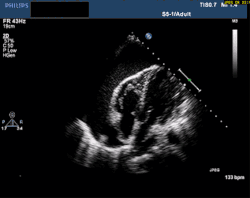

At the bedside, point-of-care echocardiography should be used.[22] This is non-invasive and can help diagnose the four types of shock.[24] Echocardiography can look for ventricular dysfunction, effusions, or valve dysfunction.[3][25] Measurement of the vena cava during the breathing cycle can help assess volume status.[22][24] A point-of-care echocardiogram can also assess for causes of obstructive shock. The vena cava would be dilated due to the obstruction. In pulmonary embolism, the right ventricle will be dilated. Other findings include paradoxical septal motion or clots in the right heart or pulmonary artery. Echocardiography can assess for pericardial effusion. In tamponade, collapse of the right atrium and ventricle would be seen due to pressure in the pericardial sac.[24]

A PE is considered "massive" when it causes hypotension or shock. A submassive PE causes right heart dysfunction without hypotension.[18]

Cardiac tamponade

A pericardial effusion is fluid in the pericardial sac. When large enough, the pressure compresses the heart. This causes shock by preventing the heart from filling with blood. This is called cardiac tamponade. The chambers of the heart can collapse from this pressure. The right heart has thinner walls and collapses more easily. With less venous return, cardiac output decreases. The lack of blood flow to vital organs can cause death.[19]

Whether an effusion causes tamponade depends on the amount of fluid and how long it took to accumulate. When fluid collects slowly, the pericardium can stretch. Thus, a chronic effusion can be as large as 1 liter.[20] Acute effusions can cause tamponade when small because the tissue does not have time to stretch.[21]